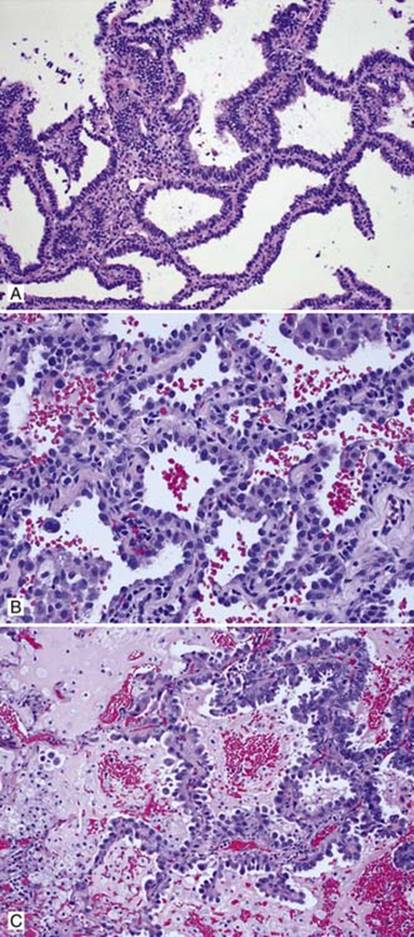

Fig 2 Adenocarcinoma in situ. Nonmucinous AIS: A, columnar cells growing along alveolar septae; B, cuboidal tumor cells; and C, nonmucinous AIS with associated obstructive pneumonitis leading to accumulation of intraalveolar mucin and muciphages.